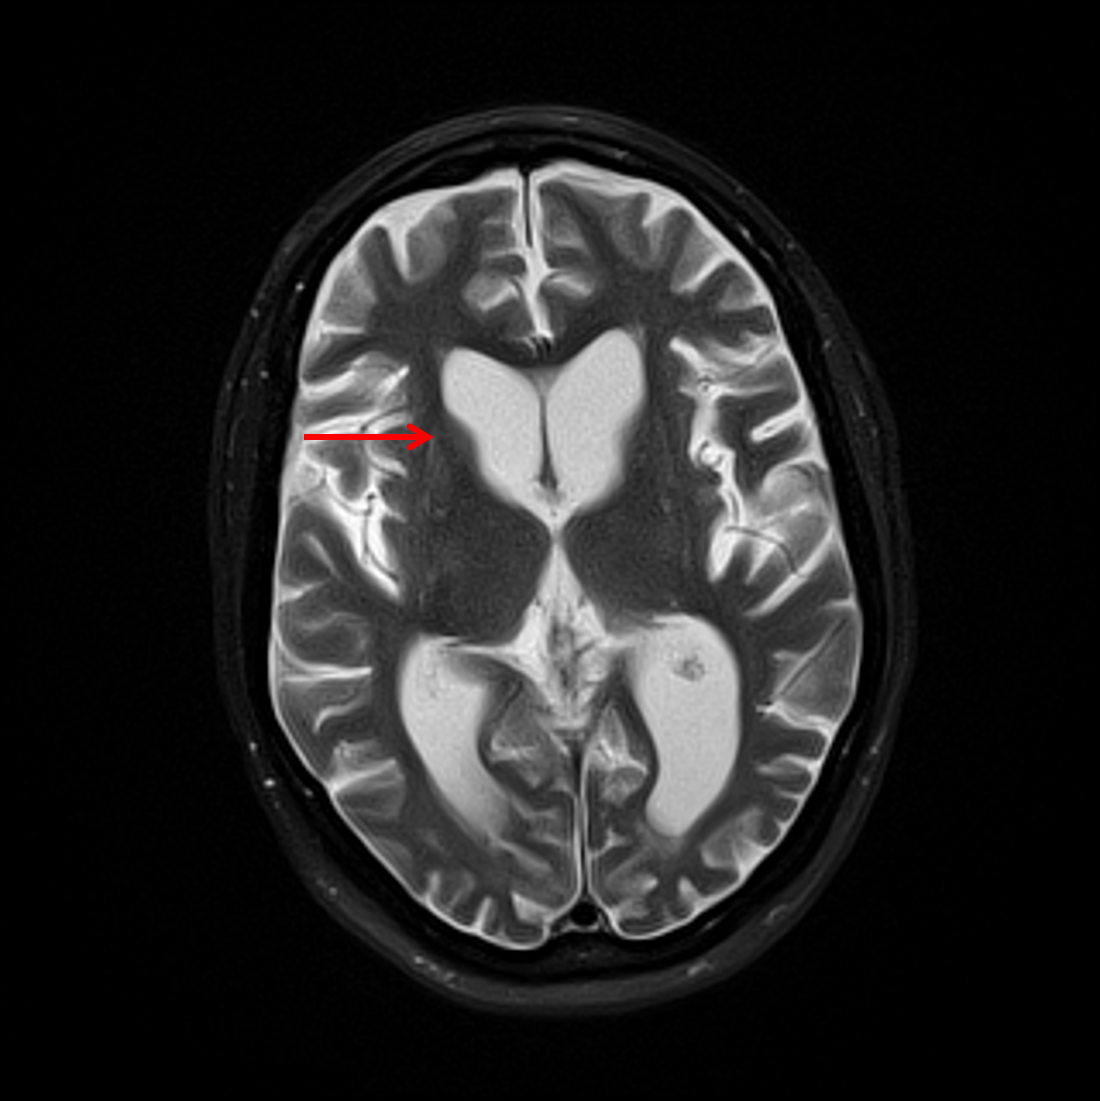

Age: 45

Sex: Female

Indication: Psychosis

Huntington disease

Sample ReportMarked atrophy of the caudate and putamen bilaterally on a background of age-advanced generalized cerebral volume loss. These findings can be seen in the setting of Huntington disease.

No acute intracranial abnormality.